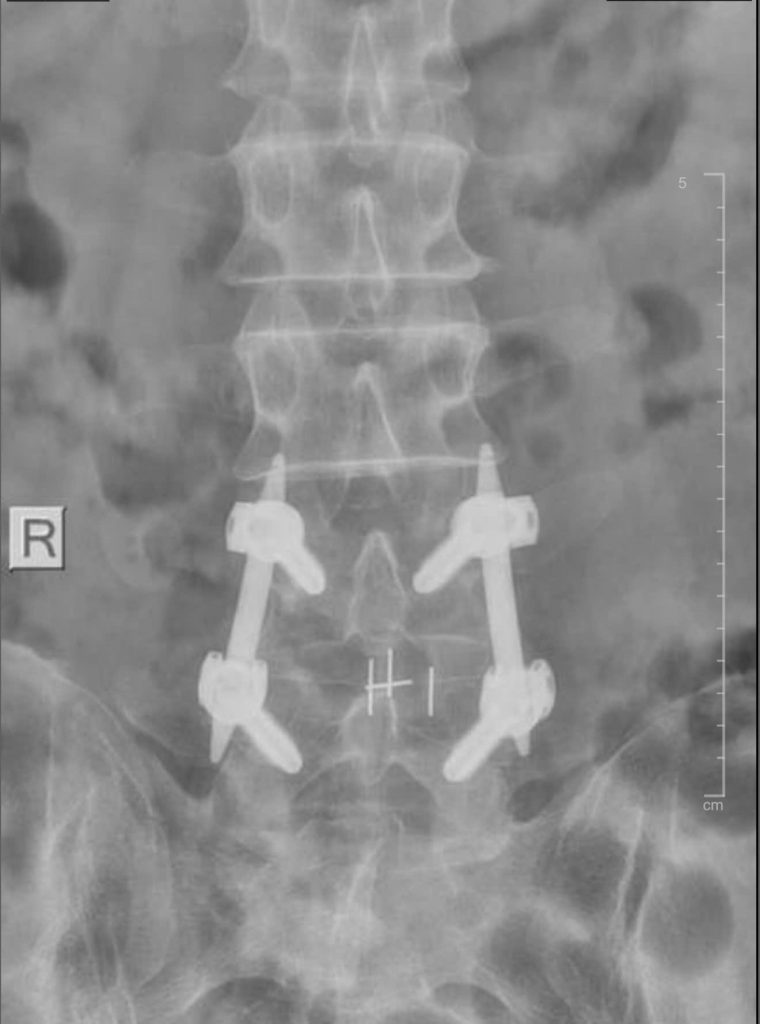

Đến khám tại BVĐK Xuyên Á Vĩnh Long, bệnh nhân được các bác sĩ khoa Ngoại Thần Kinh thăm khám kỹ lưỡng và chỉ định các cận lâm sàng cần thiết. Kết quả chụp cộng hưởng từ (MRI) 1.5 Tesla cho thấy bệnh nhân bị thoát vị đĩa đệm đốt sống thắt lưng L4 –> L5, chèn ép đường đi của rễ thần kinh hai bên.

Hình ảnh MRI của bệnh nhân thực hiện bắt vít qua da

Việc phẫu thuật để điều trị là rất cần thiết. Tuy vậy, bệnh nhân vô cùng lo lắng và phân vân. Trong trường hợp này, các bác sĩ tư vấn áp dụng phương pháp bắt vít qua da để điều trị, thay vì phải mổ hở. Với sự giải thích tận tình của các bác sĩ, bệnh nhân và gia đình yên tâm đồng ý phẫu thuật.